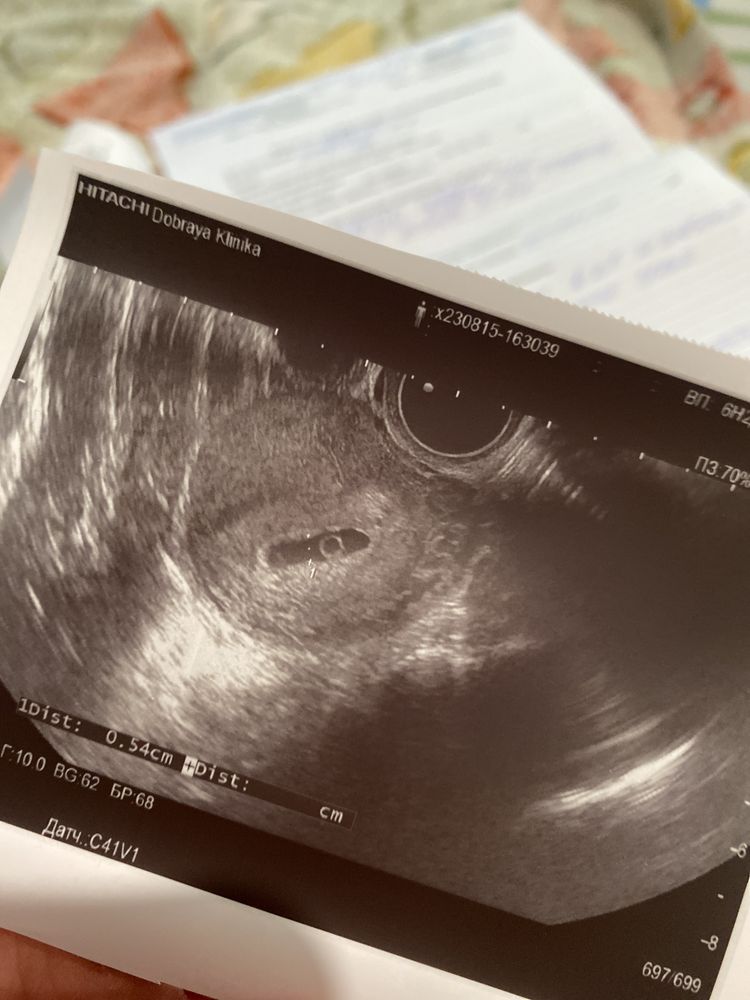

Не видно эмбриона 6нед+3

Полина , по моему опыту узист должен быть слепой и с советским аппаратом, чтобы не заметить эмбрион, когда он появится. Картинка у вас вроде качественная, просто рано ещё, буквально пару дней.

Эмбрион видно на УЗИ при ХГЧ больше 5000, пока ещё рано. Я ждала 7 недели, чтоб уж точно увидеть. А желточный мешочек есть уже? Если да, то и эмбриончик рядом скорее всего

Полина,Хгч 12 дней назад был 3200,желточный есть

На счет формы плодного яйца вам ничего не сказали? Возможно был тонус во время узи, оно слишком вытянутое. А так есть какой-то бугорок на желточном мешочке, возможно во время тонуса эмбриончик вжался в стенку плодного яйца и поэтому плохо его видно. Пульсация есть?

Ася, сказали что немного неправильной формы,у меня потягивал немного живот на 4-5 неделе,1 раз довольно сильней чем обычно,это было утром сильно в туалет хотелось,и боль прошла минут через 5,но я думаю это из-за того что довольно резко вставили датчик и я естественно вся сжалась

Полина , как по мне, так он там есть, крохотный просто еще. Денька три подождать, должен уже получше визуализироваться.

Эмбрион часто не видно если меньше 7 недель, лучше идти попозже. Желточный мешочек есть, значит и эмбрион скоро появится.

Да вроде бы что-то виднеется беленькое. Подождите еще. Главное - в матке, дайте ему шанс))